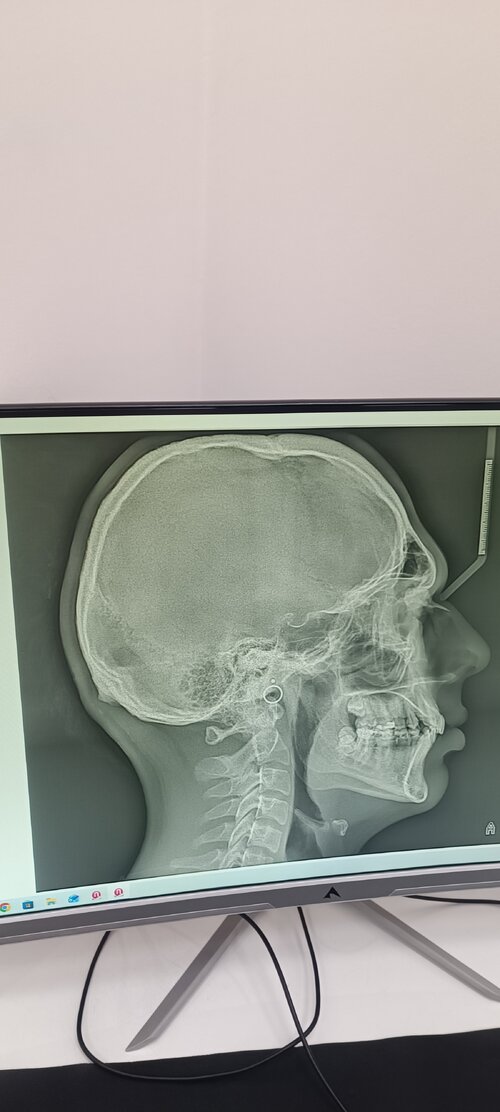

mandibular plane angle definitely not ideal

counter clockwise tri with segmental lefortwhat surg u getting bhai?